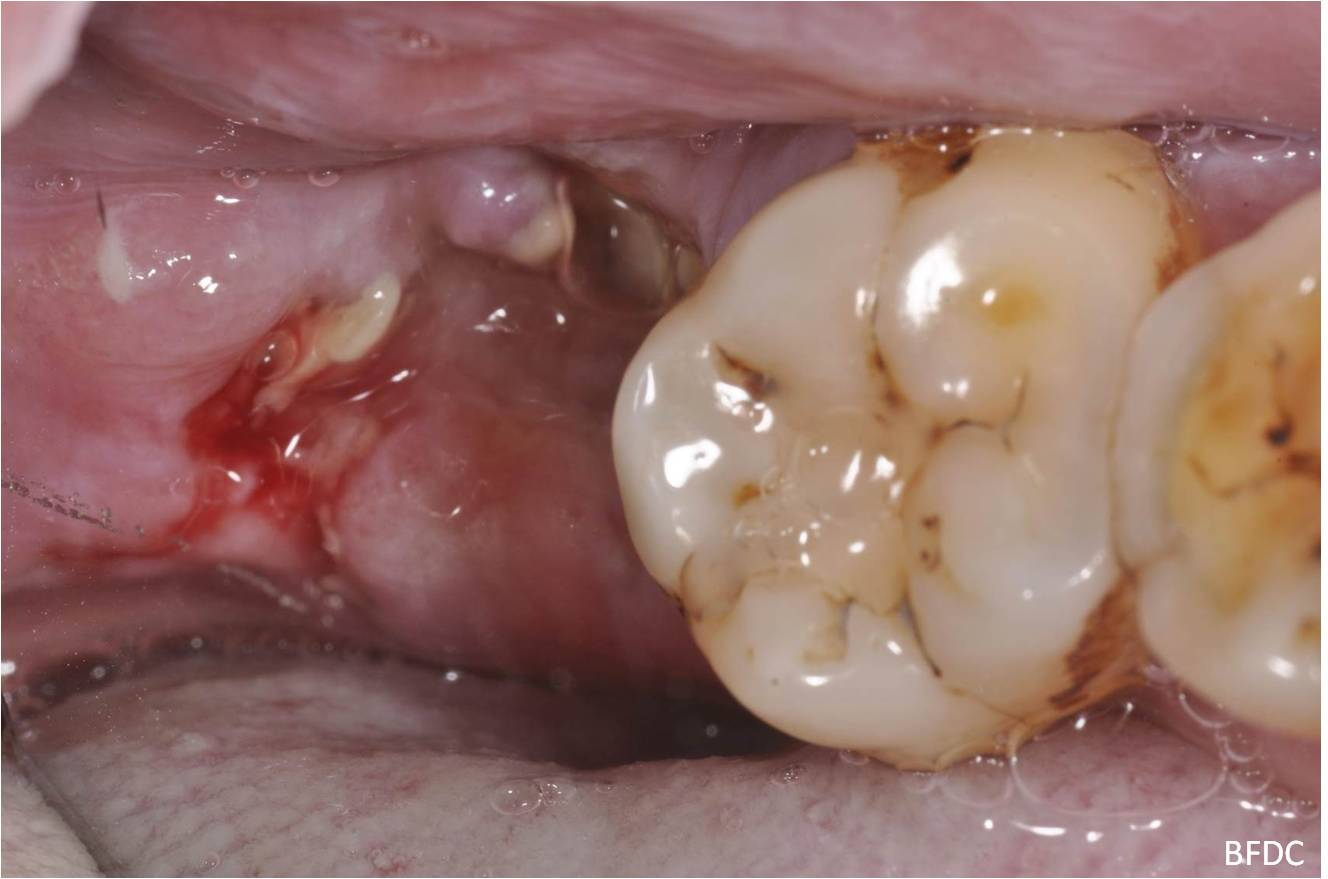

治療後,骨缺損修復

一週後,傷口逐漸癒合

使用骨質增生膠原蛋白,來處理拔牙後的傷口。此材料適用的範圍不僅用於拔牙後傷口,所有顎骨中的病灶於手術後皆建議使用。

因此在拔牙後的傷口如果可合併骨原修復傷口,對傷口癒合,有相當的幫助。